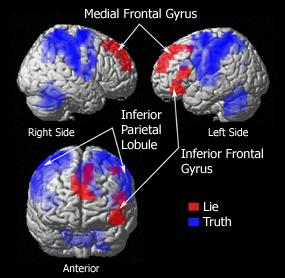

Lie detection with fMRI

Note:

build a new age lie detector